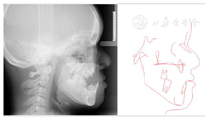

,反覆盖10mm,双侧尖牙及磨牙近中关系;51、61扭转,上颌牙弓狭窄,腭盖高拱,31、41间可见间隙约5mm(图2)。(3)影像学检查:①曲面断层片示多数乳牙滞留,恒牙迟萌,多颗埋伏阻生多生牙。54、64远中邻面低密度影及髓,牙根吸收(图3);②CBCT示全口恒牙排列紊乱,上下颌骨内可见13颗多生牙,均位于恒牙胚舌腭侧,形态类似相邻恒牙胚(图4);③头颅侧位片示头颅侧位片示上颌骨发育不足(NA-Apo:-5.9°),下颌前突(SNB: 98.2°;FH-NPo:90.0°),骨性III类错

畸形(ANB:-5.1°;FMA:31.0°)(图5)(表1);④头颅正位片示颅缝轻微增宽;⑤胸片示双侧锁骨远心端发育不足(图6)。